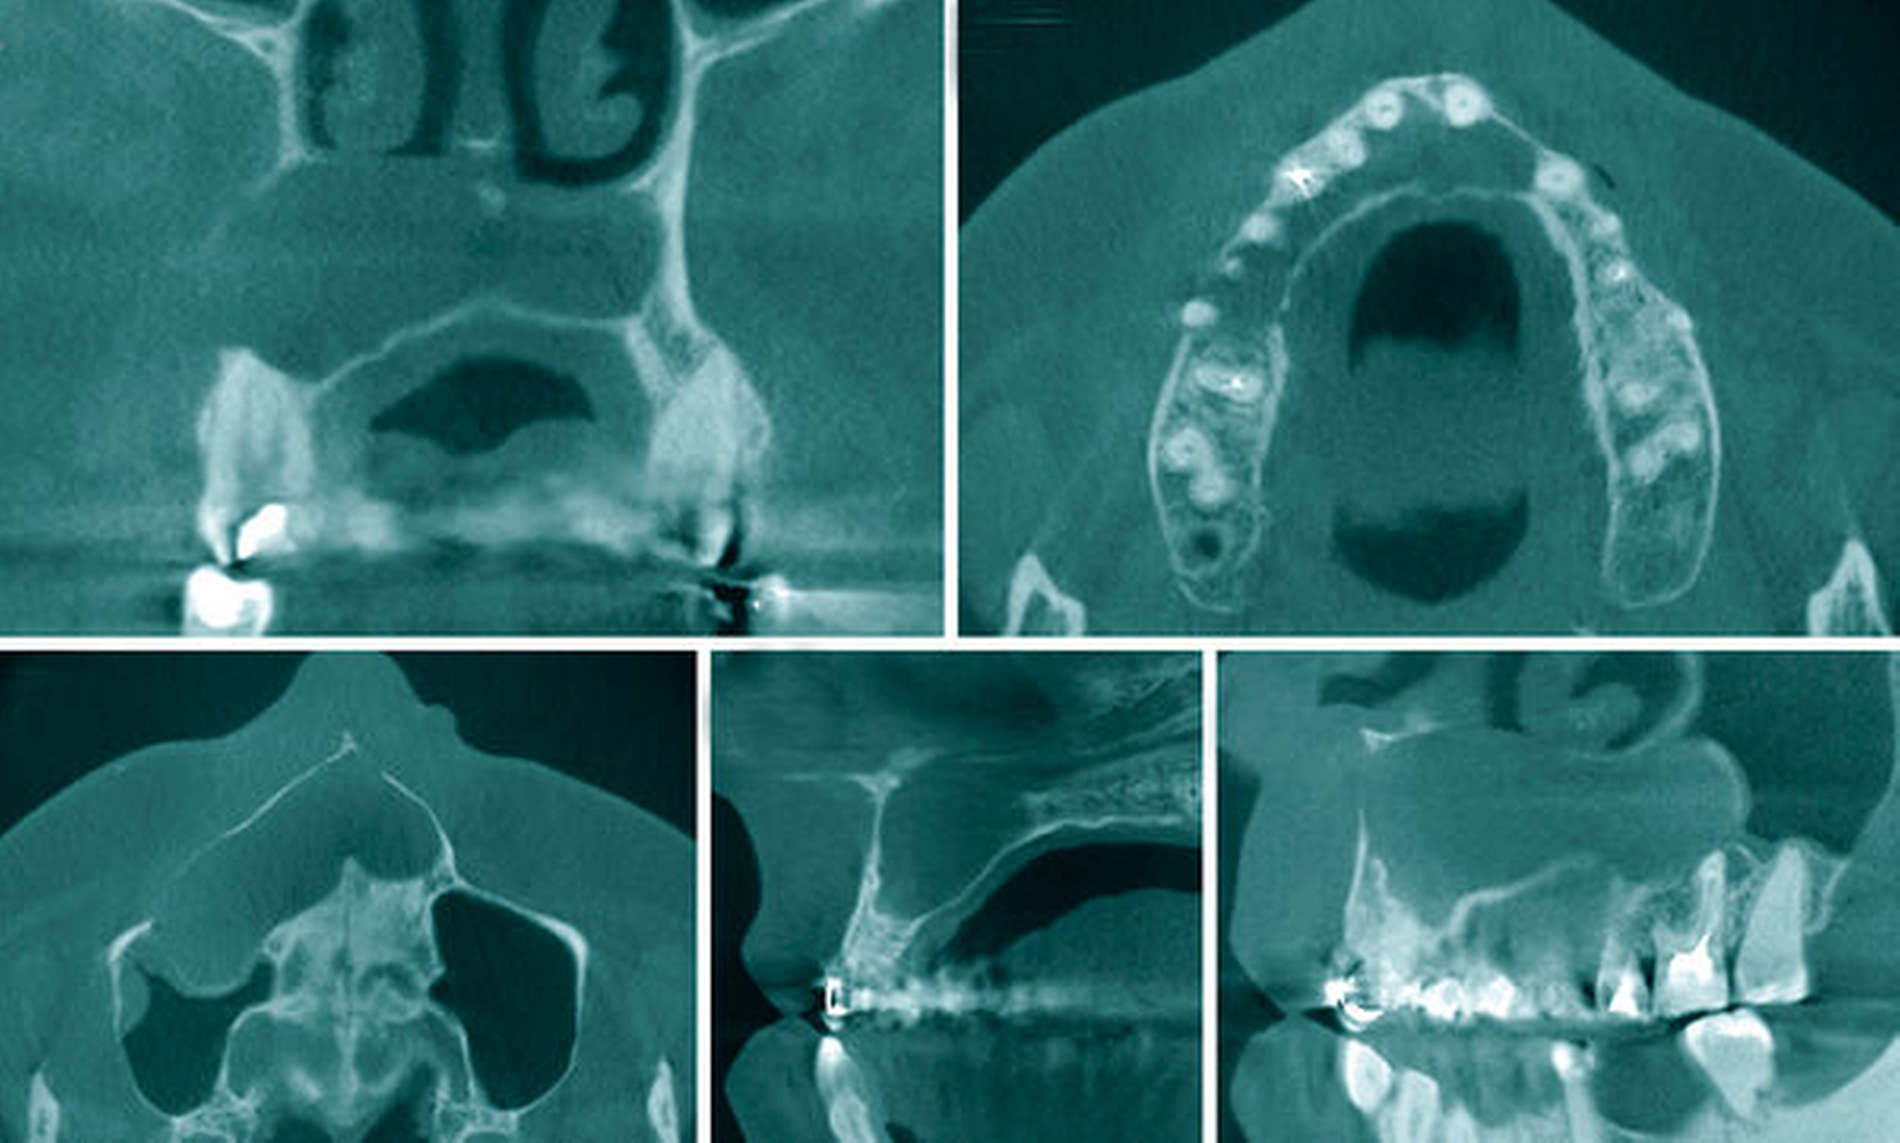

Eine 37-jährige Patientin stellte sich zur Weiterbehandlung einer radiologisch auffälligen Raumforderung im Bereich des Oberkiefers in unserer Ambulanz vor. Das vorhandene Orthopantomogramm (Abbildung 1) zeigte neben dem aktuellen Zahnstatus mit den bereits endodontisch behandelten Zähnen 16, 15, 13 und 25 sowie den implantologisch ersetzten Zähnen 36 und 37 eine zystische Raumforderung von regio 16 bis 23. Klinisch reagierten die Zähne 14, 12, 11, 21 und 23 auf Kälte sensibel. Es bestanden keine Zahnlockerungen. Vestibulär in regio 13 bis 15 stellte sich eine Knochenauftreibung mit auslösbarem, pergamentartigem Knistern dar. Zur dreidimensionalen Darstellung der Zyste wurde ein DVT des Oberkiefers erstellt (Abbildung 2).